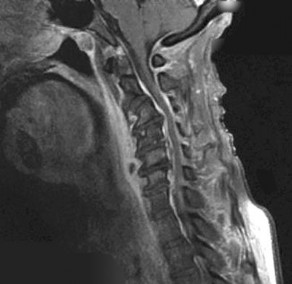

A 65-year-old male presents with progressive clumsiness in his hands, difficulty buttoning his shirt, and a wide-based gait. Physical exam reveals a positive Hoffmann's sign bilaterally.

MRI of the cervical spine demonstrates multilevel degenerative spondylosis with cord compression. Which of the following MRI findings is considered the strongest independent predictor of a poor neurologic recovery following surgical decompression?